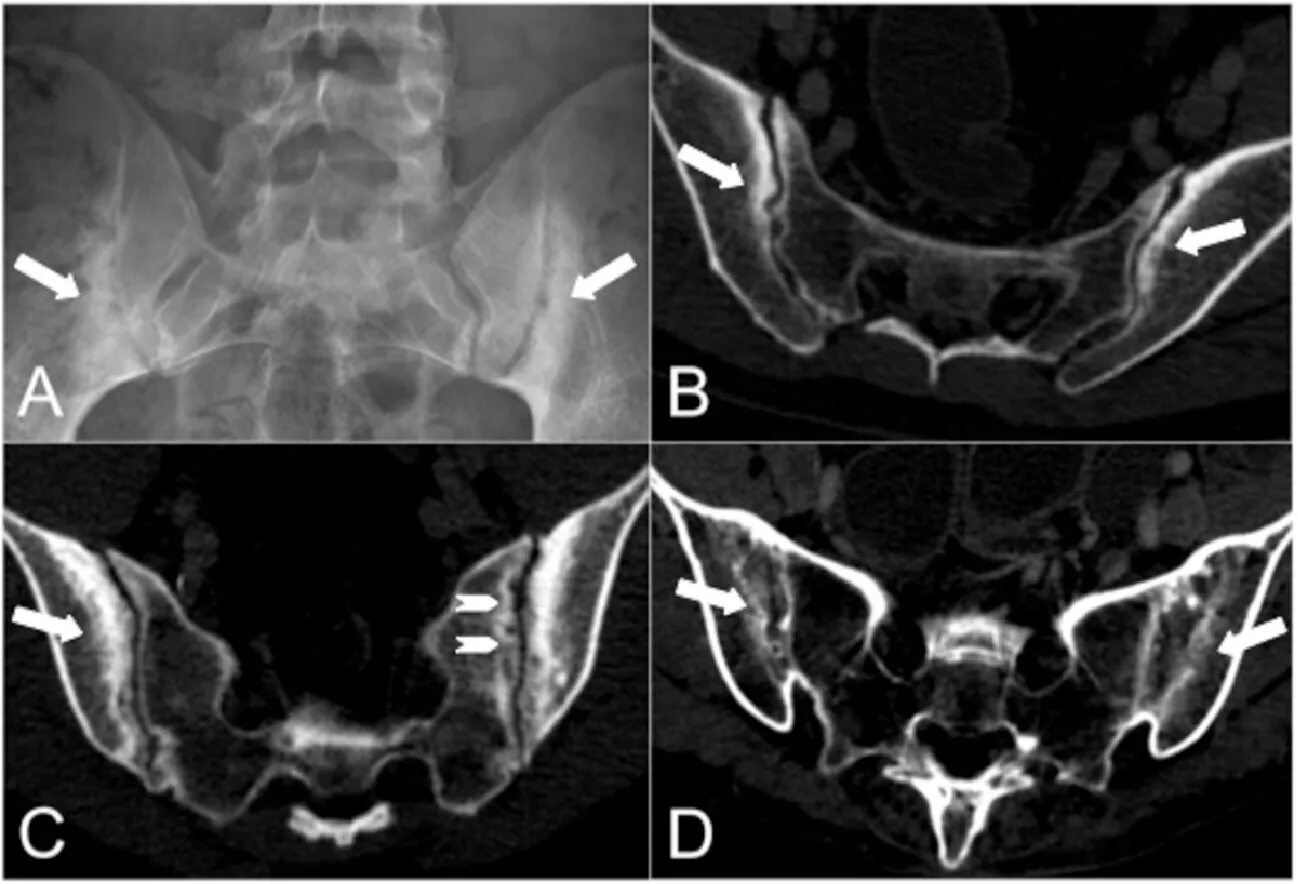

Сакроилеит на кт